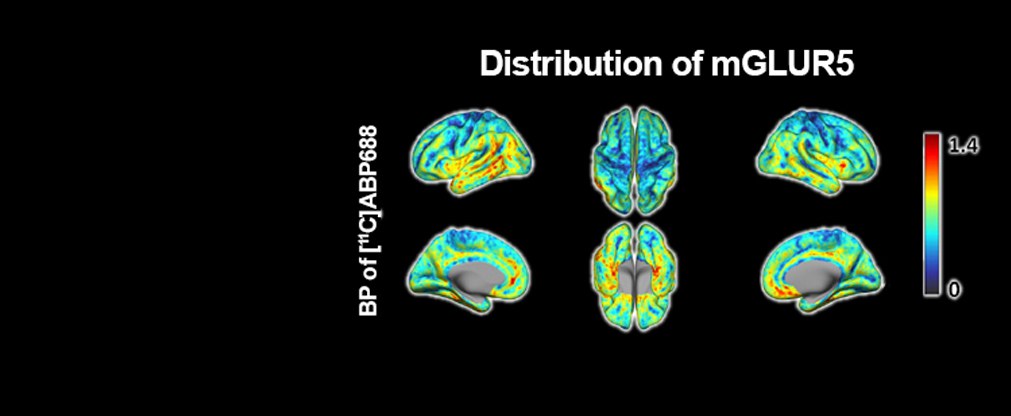

Die Forschungs- und Entwicklungsarbeiten unserer Institutsbereiche der Physik der Medizinischen Bildgebung (INM-4) des Instituts für Neurowissenschaften konzentrieren sich auf die Entwicklung, experimentelle Validierung und klinische Prüfung neuer Bildgebungsmethoden des Gehirns.

Jülicher Bildgebungstechnik ermöglicht präzise Einblicke in Struktur und Funktion des menschlichen Gehirn